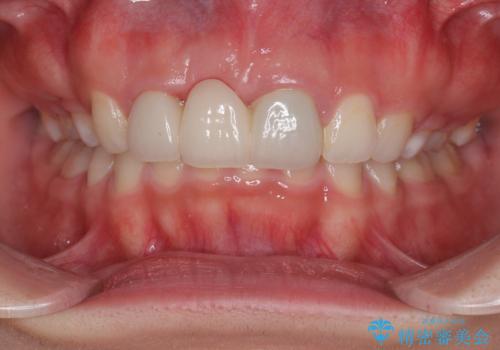

歯肉ラインを整えるために歯肉移植術を行うか悩んでいましたが、行わないという判断をされたため、やや不揃いの歯肉ラインとなりました。